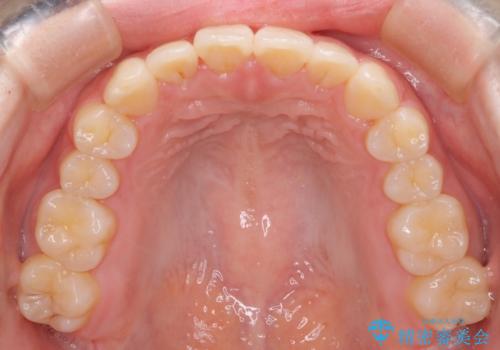

【インビザライン】前歯の凸凹をなおしたい

- 前歯のガタガタを主訴に来院されました。

インビザラインで綺麗な歯並びになり、患者さんには大変満足していただきました。

インビザラインは軽度叢生治療において優れた選択肢となります。